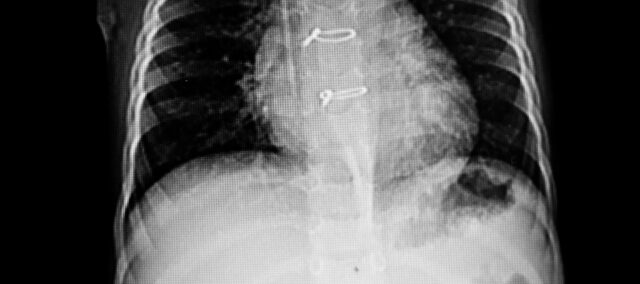

Primárním výsledkem byla sternální separace měřená pomocí ultrazvuku. Byla kvantifikována vzdálenost mezi oběma polovinami hrudní kosti a označen bod největšího oddělení. Jako sekundární výsledek byla použita stupnice nestability sterna, která hodnotí integritu sterna od stupně 0 (klinicky stabilní sternum) do stupně 3 (výrazný pohyb nebo oddělení). Měření byla provedena na začátku (7. den po operaci) a ve 4. týdnu.

Do studie bylo zařazeno 36 žen, u nichž byla ultrazvukem potvrzena akutní sternální nestabilita. Základní charakteristiky ukázaly dvě srovnatelné skupiny. Jejich základní sternální separace byla 0,23 cm.

Primární výsledek separace hrudní kosti ve 4. týdnu byl 0,13 cm v experimentální skupině a 0,22 cm v kontrolní skupině. Rozdíl mezi skupinami činil -0,09 cm (95% CI 0,07 až 0,11) ve prospěch intervenční skupiny, která po sternotomii prováděla cviky na stabilizaci trupu.